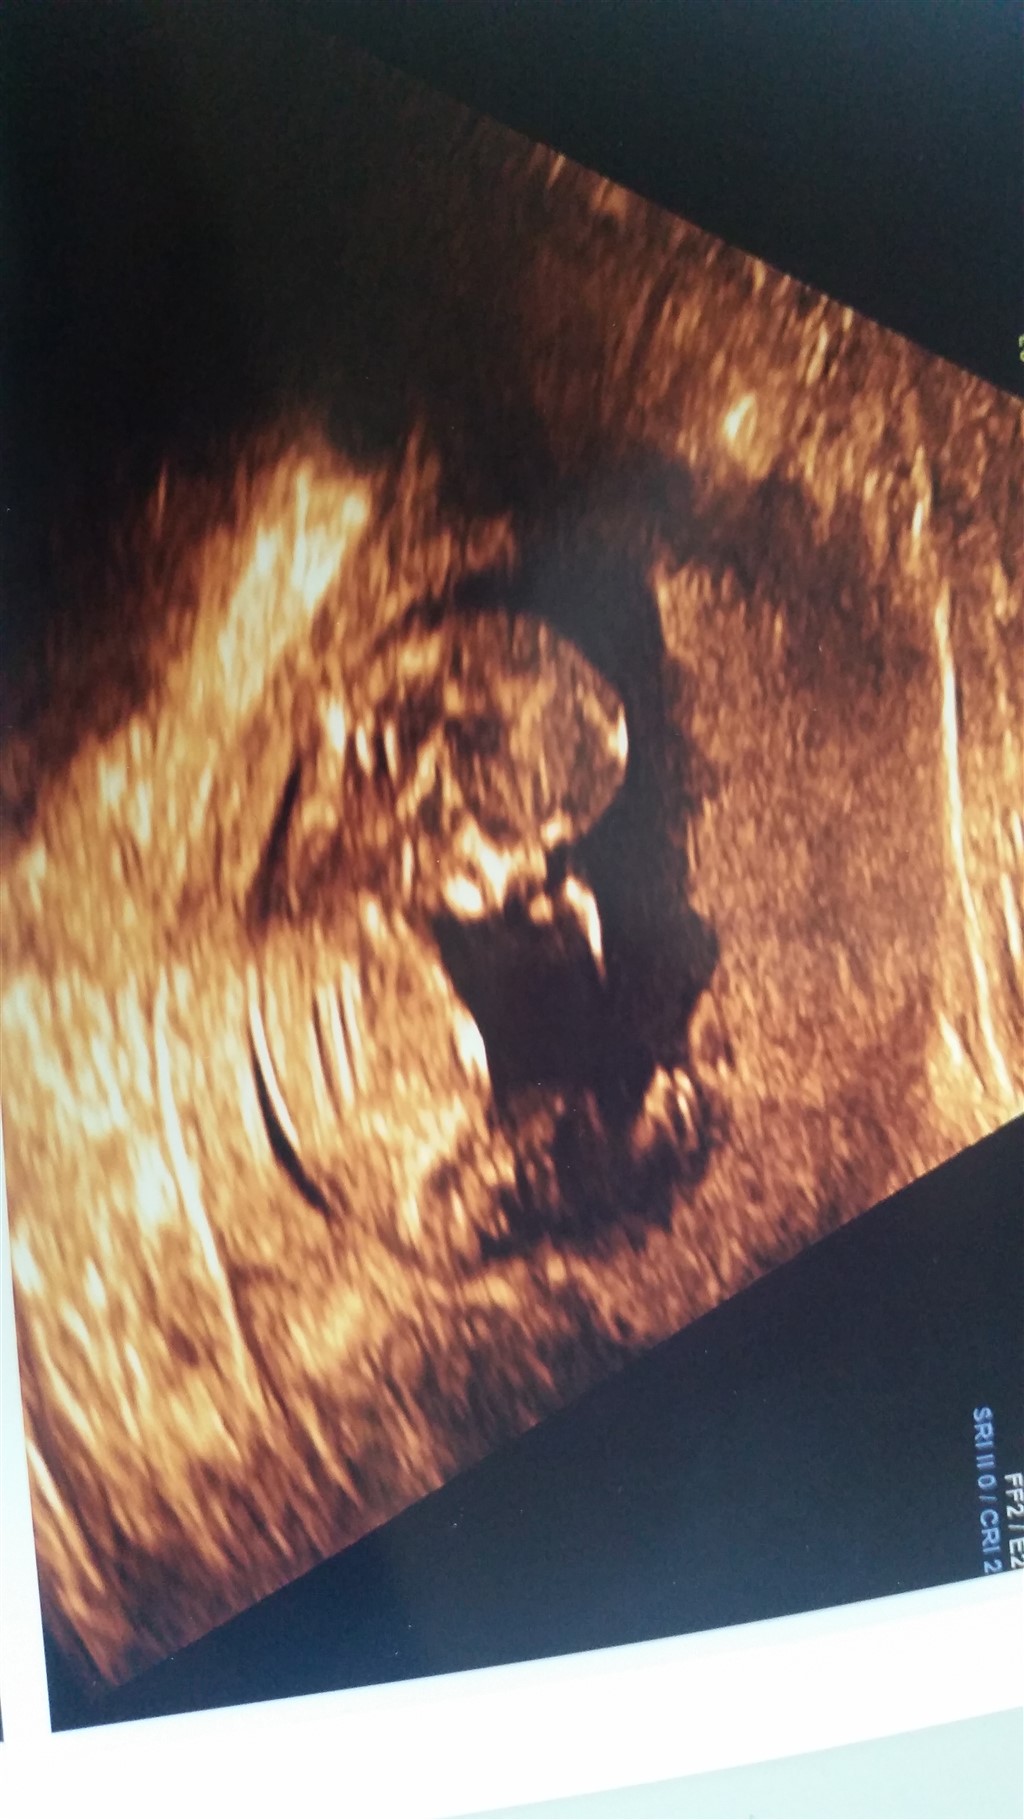

Jeg er anonym, da jeg er bange for at blive genkendt. Jeg er super spændt på at høre hvad slags køn jeg venter mig. Derfor håber jeg i har lyst til at gætte på kønnet

Tror dreng ����